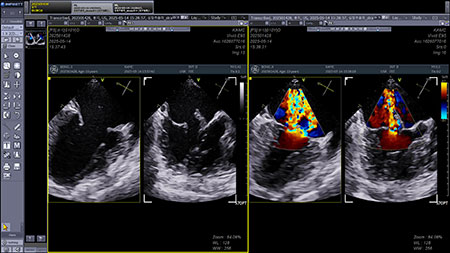

투석을 하는 동안엔 진정이 필요하니 이 아이는 다시 마취하지 말고 투석 끝날 때쯤 경식도 초음파 검사를 하는 것을 제안했다. 그리고 역시 이렇게 응급실로 밀고 들어오는 stage D 환자는 경식도초음파에서 늘 엄청난 판막 상태를 보여준다.

[그림 4] 이첨판의 앞쪽판막은 거의 모든 건삭이 끊어진 듯 했으며, 대단한 역류를 만들고 있었다. 그리고 뒤쪽판막은 3D에서 평가 시 튼튼하지 않아 보였다.

경식도 초음파를 보는 알박사는 언제나 나보다 객관적이다. ‘high risk’라고 소견을 줬고, 수술에 회의적이었다.